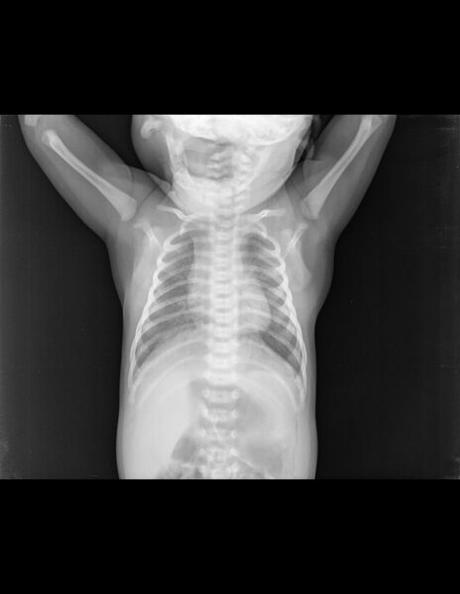

TÓRAX AP

EN LA PROYECCIÓN RADIOGRÁFICA OBTENIDA MUESTRA LOS SIGUIENTES HALLAZGOS:

Tejidos blandos simétricos, sin cambios en su densidad.

Silueta cardiomediastinica de forma habitual para la edad.

Botón aórtico, con diámetros adecuados, sin identificar calcificaciones.

Tráquea central, columna vertebral central.

Hilios pulmonares, de aspecto adecuado.

Campos pulmonares, con presencia de imágenes que simulan ser micronódulos.

Recesos cardiofrénicos y costo frénicos se observan libres.

Estructuras óseas, sin evidencia de lesiones líticas, blásticas o perdidas de la contigüidad. Fisis de crecimiento acorde a la edad.

IMPRESIÓN DIAGNOSTICA:

EN EL PRESENTE ESTUDIO RADIOGRÁFICO, CON IMÁGENES SUGERENTE DE BRONQUIOLITIS.

CORRELACIONAR CON DATOS CLÍNICOS Y ANTECEDENTES DE CONSIDERARSE NECESARIO POR MÉDICO TRATANTE, COMPLEMENTAR CON ESTUDIOS ADICIONALES O DE CONTROL, SEGÚN EVOLUCIÓN CLÍNICA DEL PACIENTE.